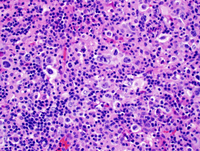

Small lymphocytic lymphoma with Richter's Syndrome, Hodgkin type.

H&E showing the small lymphocytes in the background of large atypical cells consistent with Hodgkin cells.